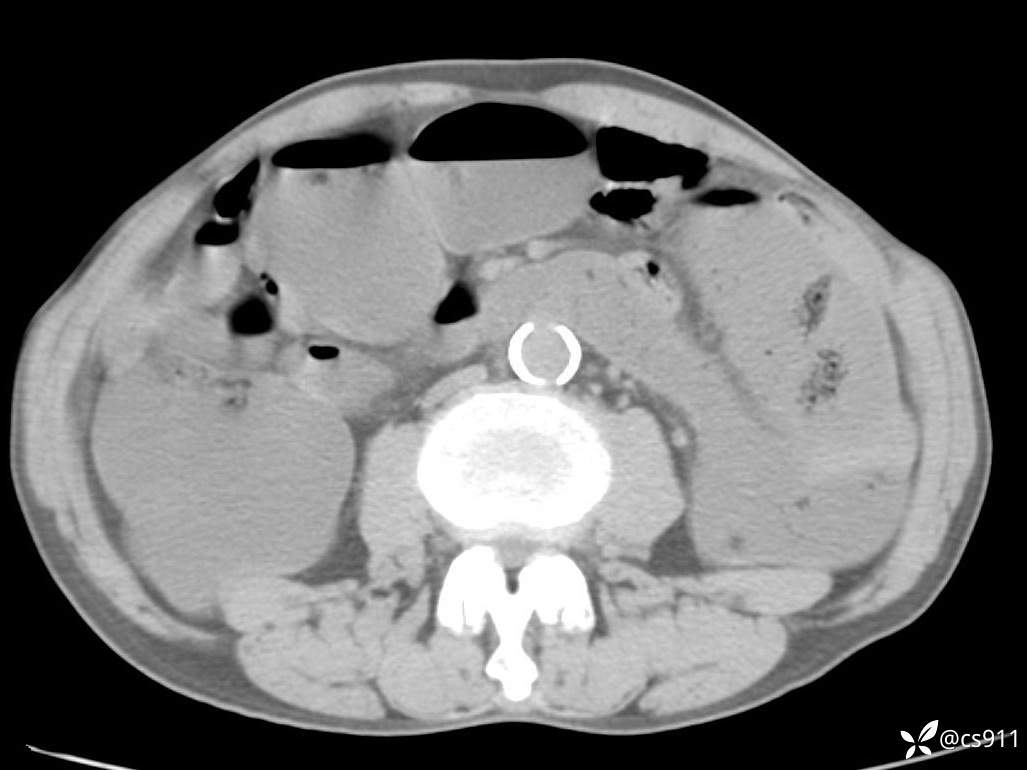

急腹症之急诊CT,原因?答案公布

男,77岁,腹痛、腹胀伴恶心呕吐1天。呕吐胃内容物,非喷射性呕吐,有咖啡色样胃内容物,诉有胃穿孔病史。查体:全腹平,下腹部压痛,全腹无反跳痛,叩诊呈浊音,移动性浊音阴性,肠鸣音减弱,1-2次/分。肛检:直肠未扪及明显肿物,可触及大量粪块。

T 36.6℃ P 80次/分 R 26次/分 BP 100/60mmHg

白细胞(WBC) H 14.55 10e9/L 4-10

中性粒细胞百分率(NEUT%) H 85.7 % 40-75

血淀粉酶(AMY) HH 1859 U/L 35-135

癌胚抗原(CEA) H 27.44 ng/ml 0-5

呕吐物 潜血试验 * 阳性 阴性

患者轮椅入室检查神志清楚, 能配合摆位和呼吸